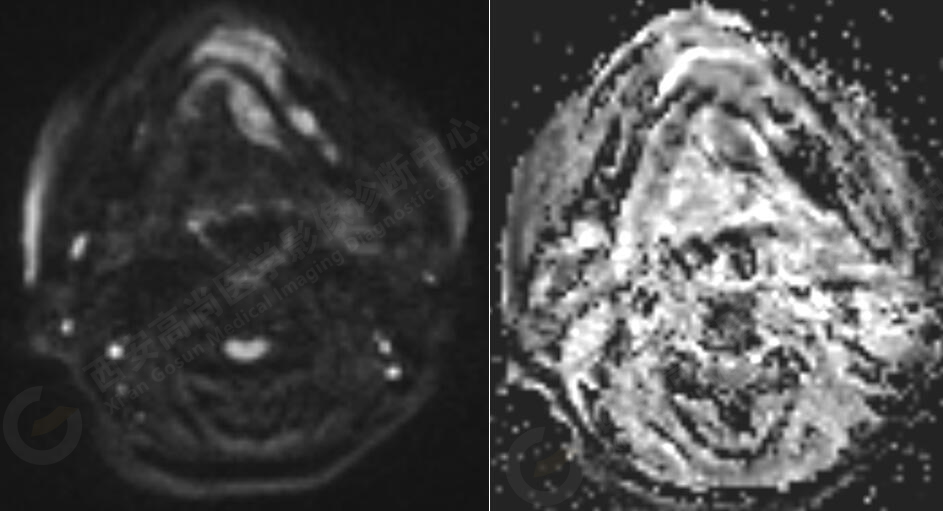

MR平掃+增強(qiáng):左側(cè)口底部下頜骨周圍見大小約3.4cmX3.3cmX3.3cm的團(tuán)塊狀稍長(zhǎng)T1稍長(zhǎng)T2信號(hào),壓脂像上呈稍高信號(hào),病灶邊緣清晰,形態(tài)不規(guī)則,下頜骨骨質(zhì)破壞,強(qiáng)化掃描示:左側(cè)下頜骨周圍病灶呈不均勻明顯強(qiáng)化,邊緣強(qiáng)化為著。

此腫瘤位于左側(cè)口底部下頜骨周圍,未見明顯囊變,下頜骨骨質(zhì)破壞,DWI像上病灶呈明顯低信號(hào),ADC圖上呈低信號(hào),增強(qiáng)后不均勻明顯強(qiáng)化,病人年齡較大,可以考慮惡性腫瘤,口底好發(fā)鱗癌。